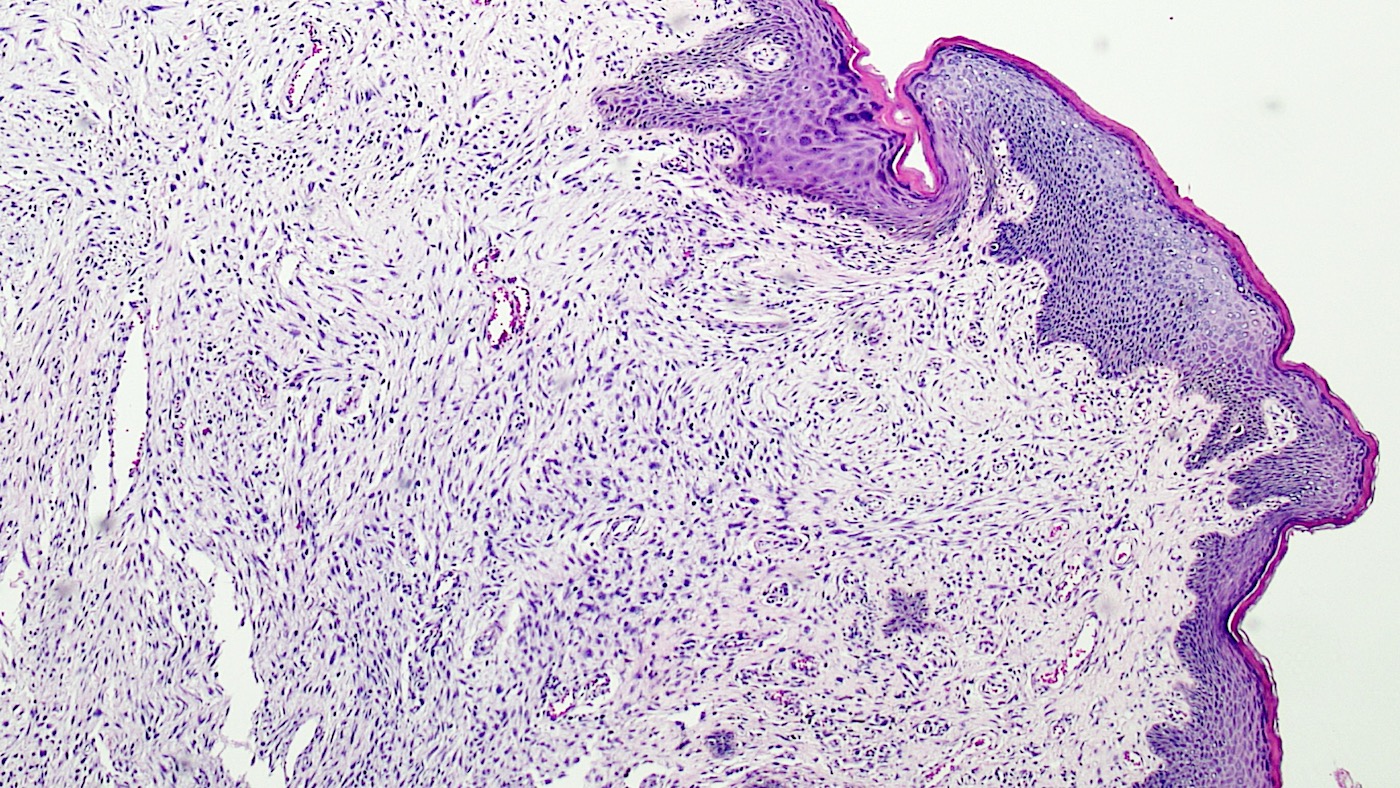

Microscopic (histologic) description

- Polypoid and noncircumscribed, extending to the epithelial / subepithelial interface (J Low Genit Tract Dis 2011;15:69, Am J Surg Pathol 2000;24:231)

- 2 stromal cellularity variants: hypocellular form (spindle cells set within a loose collagenous myxoid-like stroma) or hypercellular variant (exhibits marked nuclear pleomorphism and frequent mitoses, including atypical forms), especially during pregnancy, therefore mimicking leiomyosarcoma or rhabdomyosarcoma (Am J Surg Pathol 2000;24:231)

- Overlying squamous epithelium may display reactive changes but without papillomatous architecture or koilocytosis, which distinguishes it from condyloma acuminatum (caused by human papillomavirus) (Am J Surg Pathol 2005;29:460)

- Stellate cells should not be interpreted as sarcoma (J Low Genit Tract Dis 2011;15:134)

- Commonly found around blood vessels or near the epidermal stromal interface

Microscopic (histologic) images